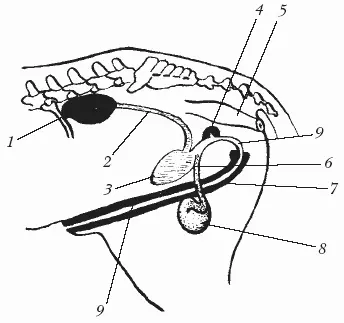

Половые органы жеребца представлены парными органами – семенниками (яичками) с придатками, семяпроводами и семенными канатиками, придаточными половыми железами – и непарными органами – мошонкой, мочеполовым каналом, половым членом и препуцием (рис. 15).

1 – почка; 2 – мочеточник; 3 – мочевой пузырь; 4 – придаточные половые железы; 5 – прямая кишка; 6 – семявыносящий проток; 7 – половой член; 8 – семенник; 9 – мочеполовой канал